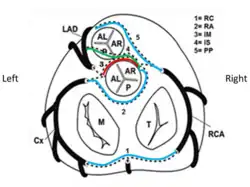

In normal anatomy, three essential coronary arteries are identified: right coronary artery (RCA), left anterior descending artery (LAD) and left circumflex artery (LCx). LAD and LCx usually originate from the bifurcation of a common vessel known as left main trunk or left coronary artery (LM or LCA).[2]

Coronary arteries are identified according to the myocardial territory they feed:[2]

1) the LAD supplies the anterior interventricular septum and anterior left ventricular free wall;

2) the LCx supplies the posterolateral left ventricular free wall;

3) the RCA supplies the right ventricular free wall;

The posterior descending artery, providing blood flow to the infero-posterior wall of the heart, originates from the RCA in 70-90% of individuals (“right coronary dominance”), whereas in 10-15% cases it originates from the LCx (“left coronary dominance”).

Several more varieties of L-ACAOS are described:

- prepulmonic (L-ACAOS-PP): origin of the LCA (or only the LAD) from the right sinus of Valsalva (RSV) with an epicardial course (on the surface of the heart) anterior to the pulmonary outflow tract - this does not usually cause stenosis nor requires intervention (benign anomaly, unless spasm occurs);

- subpulmonary, infundibular or intraseptal (L-ACAOS-SP): the LCA (or only the LAD) originates from the RSV, initially runs inter-arterially (outside the aortic wall) then intramyocardially inside in the ventricular septum and finally epicardially in the anterior interventricular groove - this anomaly is considered benign since it is not associated with significant fixed degree of stenosis (but it could cause spasm);

- retroaortic (L-ACAOS-RA): origin of the LCA or the only LCx from the RSV or from the RCA, running behind the aortic root and at the central fibrous mitro-aortic septum – this is considered as a benign anomaly (but it could cause spasm);

- retrocardiac (L-ACAOS-RC) – LCA originates from the RCA at the atrioventricular groove - or wrap-around the apex (L-ACAOS-WA) – generally benign, unless spasm occurs.